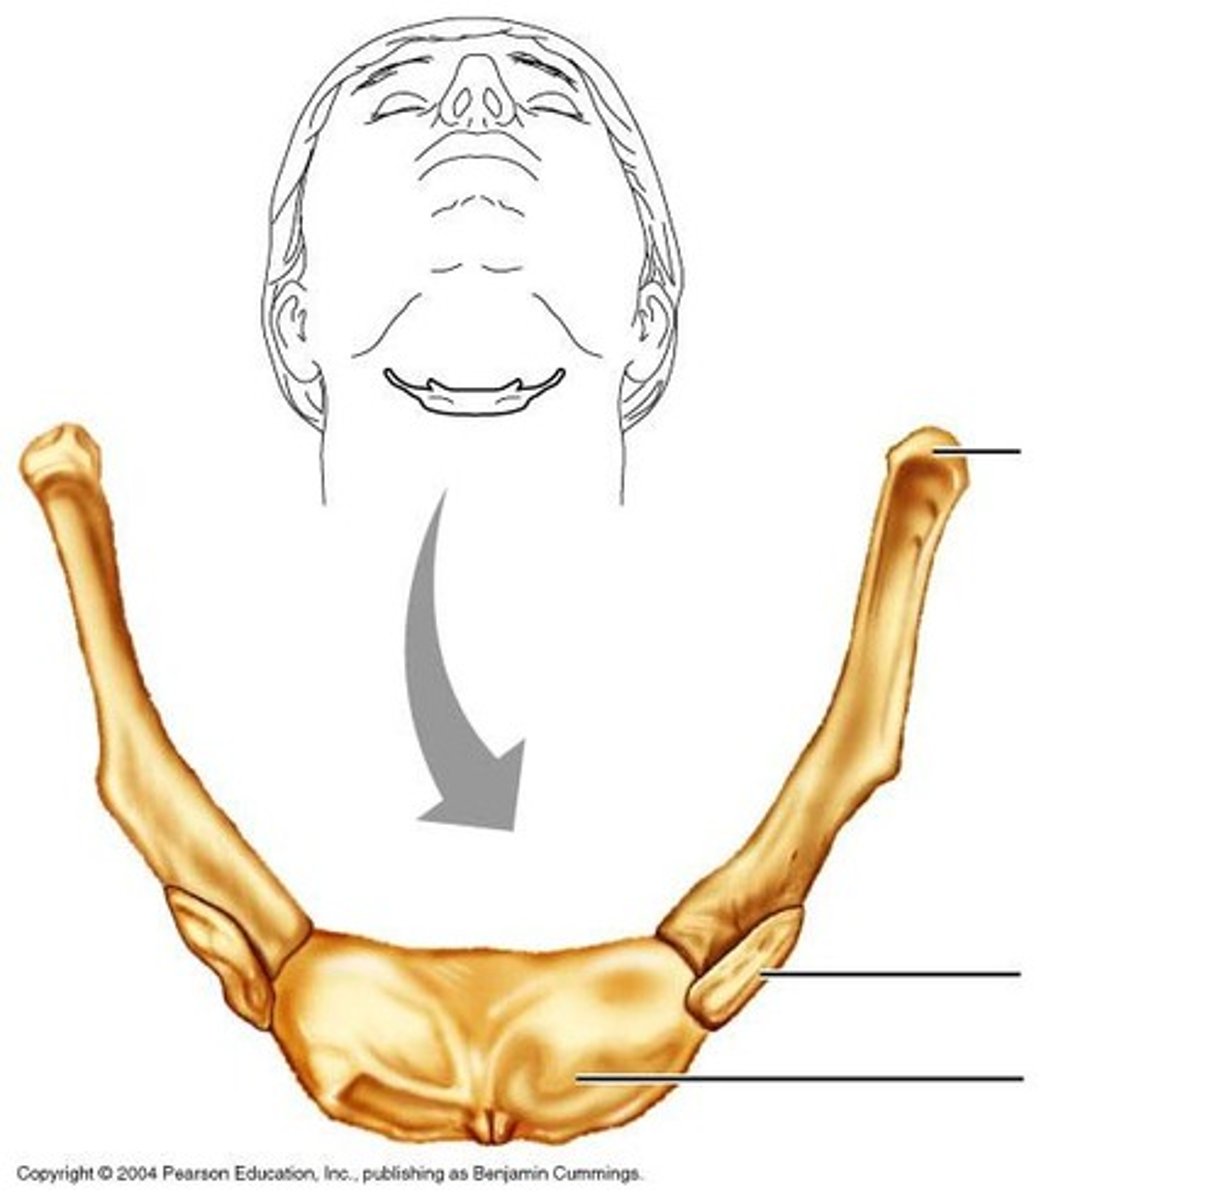

hyoid bone

What is this bone?

acromial end of clavicle

What is this structure?

sternal end of the clavicle

What is this structure?